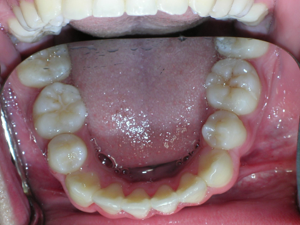

Here is what he looked like on the day that the braces were removed.

In the final photo, you can see the bonded retainer we used. A top nighttime removable retainer was made.